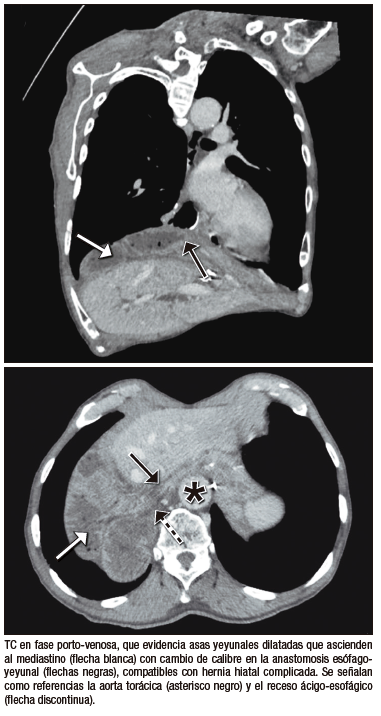

Hernia hiatal

●Caso 6. Mujer de 47 años, con antecedente de gastrectomía total y linfadenectomía por adenocarcinoma gástrico, realizada cuatro años atrás. Consultó en el servicio de urgencias por dolor abdominal agudo asociado a disnea. Se efectuó una TC de tórax, abdomen y pelvis con contraste endovenoso, que demostró una dilatación de asas yeyunales en rango patológico, las cuales ascendían a través del hiato esofágico hacia el mediastino medio. La paciente fue intervenida quirúrgicamente, confirmándose la viabilidad de las asas herniadas, por lo que se realizó reducción sin resección, con evolución favorable.

Entre las complicaciones tardías, la recidiva tumoral en la anastomosis se sospecha en TC por engrosamiento mural focal, siendo el diagnóstico definitivo histológico.12 La úlcera perianastomótica puede manifestarse con abdomen agudo, y en TC se identifica como un defecto focal de la mucosa con burbujas de gas extraluminales.13 La hernia hiatal complicada, en tanto, constituye una causa de obstrucción intestinal diferida; la TC permite evidenciar el ascenso de asas al mediastino y el punto de transición, diferenciándose de otras causas, como bridas o hernias internas.14